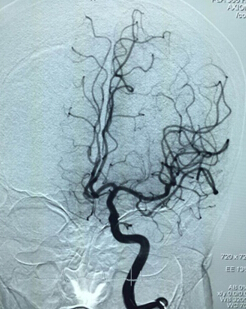

就在大家刚刚松了一口气的时候,脱落后的血栓竟然随着血流堵住了左侧另一只大血管——左侧大脑前动脉,造影显示,左侧另一只大血管的“树枝”慢慢消失了。现场指挥蔡艺灵当机立断,迅速开展第二次取栓,当神经血管重建装置在左侧大脑前动脉血管内释放展开时,即刻造影提示左侧大脑前动脉血流部分再度通畅,这一次,装置前段牢牢抓住了“逃跑”的血栓,将取栓装置撤出体外后,取出了大块的暗红色血栓。

左侧大脑前动脉被脱落血栓块栓塞

造影提示左侧颈内动脉血管均已开通